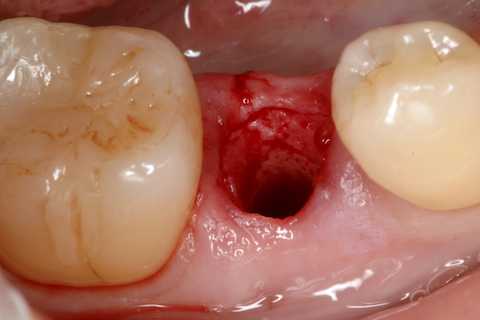

今日の抜歯再植術シリーズ39.2 2025.11.15